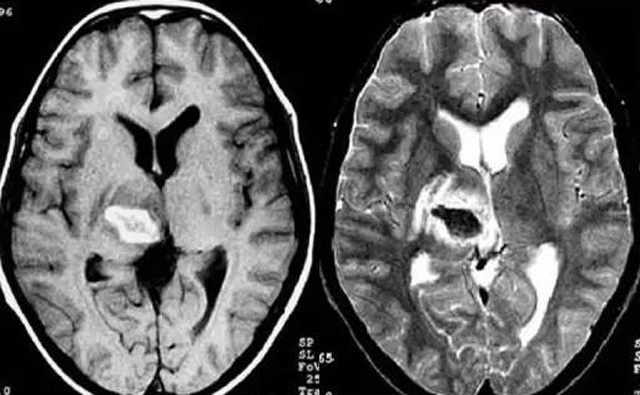

發(fā)現(xiàn)病人出血腦梗相關(guān)癥狀時候第一時間就醫(yī),需要攜帶以往的影像檢查資料。向醫(yī)生提供相關(guān)的病史基本資料。做影像檢查時候需要全身不攜帶金屬物品。檢查時候身體保持不動,不然偽影對檢查結(jié)果有干擾。磁共振MRI發(fā)現(xiàn)缺血性卒中后,幫助進一步查找病因。由于CT上小腦跟腦干顱骨影響,容易導(dǎo)致漏診。MRI檢查可以對CT檢查不足的補充。短暫的腦缺血TIA也需要進行影像檢查。短暫性缺血一般10幾分鐘后好轉(zhuǎn)。檢查目的可以確定TIA的病因。降低腦梗死的發(fā)生率。磁共振有助于排出TIA表現(xiàn)的顱內(nèi)病變,有診斷及時治療的價值。磁共振MRI檢查時間比較長,不太適合急診病人。但是可以發(fā)現(xiàn)腦干小腦的出血問題。因為急性腦梗死的早期和急性期,缺血區(qū)的腦組織還沒有完全壞死,頭顱CT不能顯示病灶,所以就需要MRI磁共振檢查,這個對陳舊跟亞急性出血顯示比較好。缺點性價比不高,費用比較貴。頭顱的磁共振MRI在發(fā)病后的幾天CT的敏感降低時候發(fā)揮大作用。,MRI可作為診斷蛛網(wǎng)膜下腔出血和了解破裂動脈瘤部位的一種重要方法,必要時進一步進行DSA檢查,幫助制訂臨床的手術(shù)治療方案,